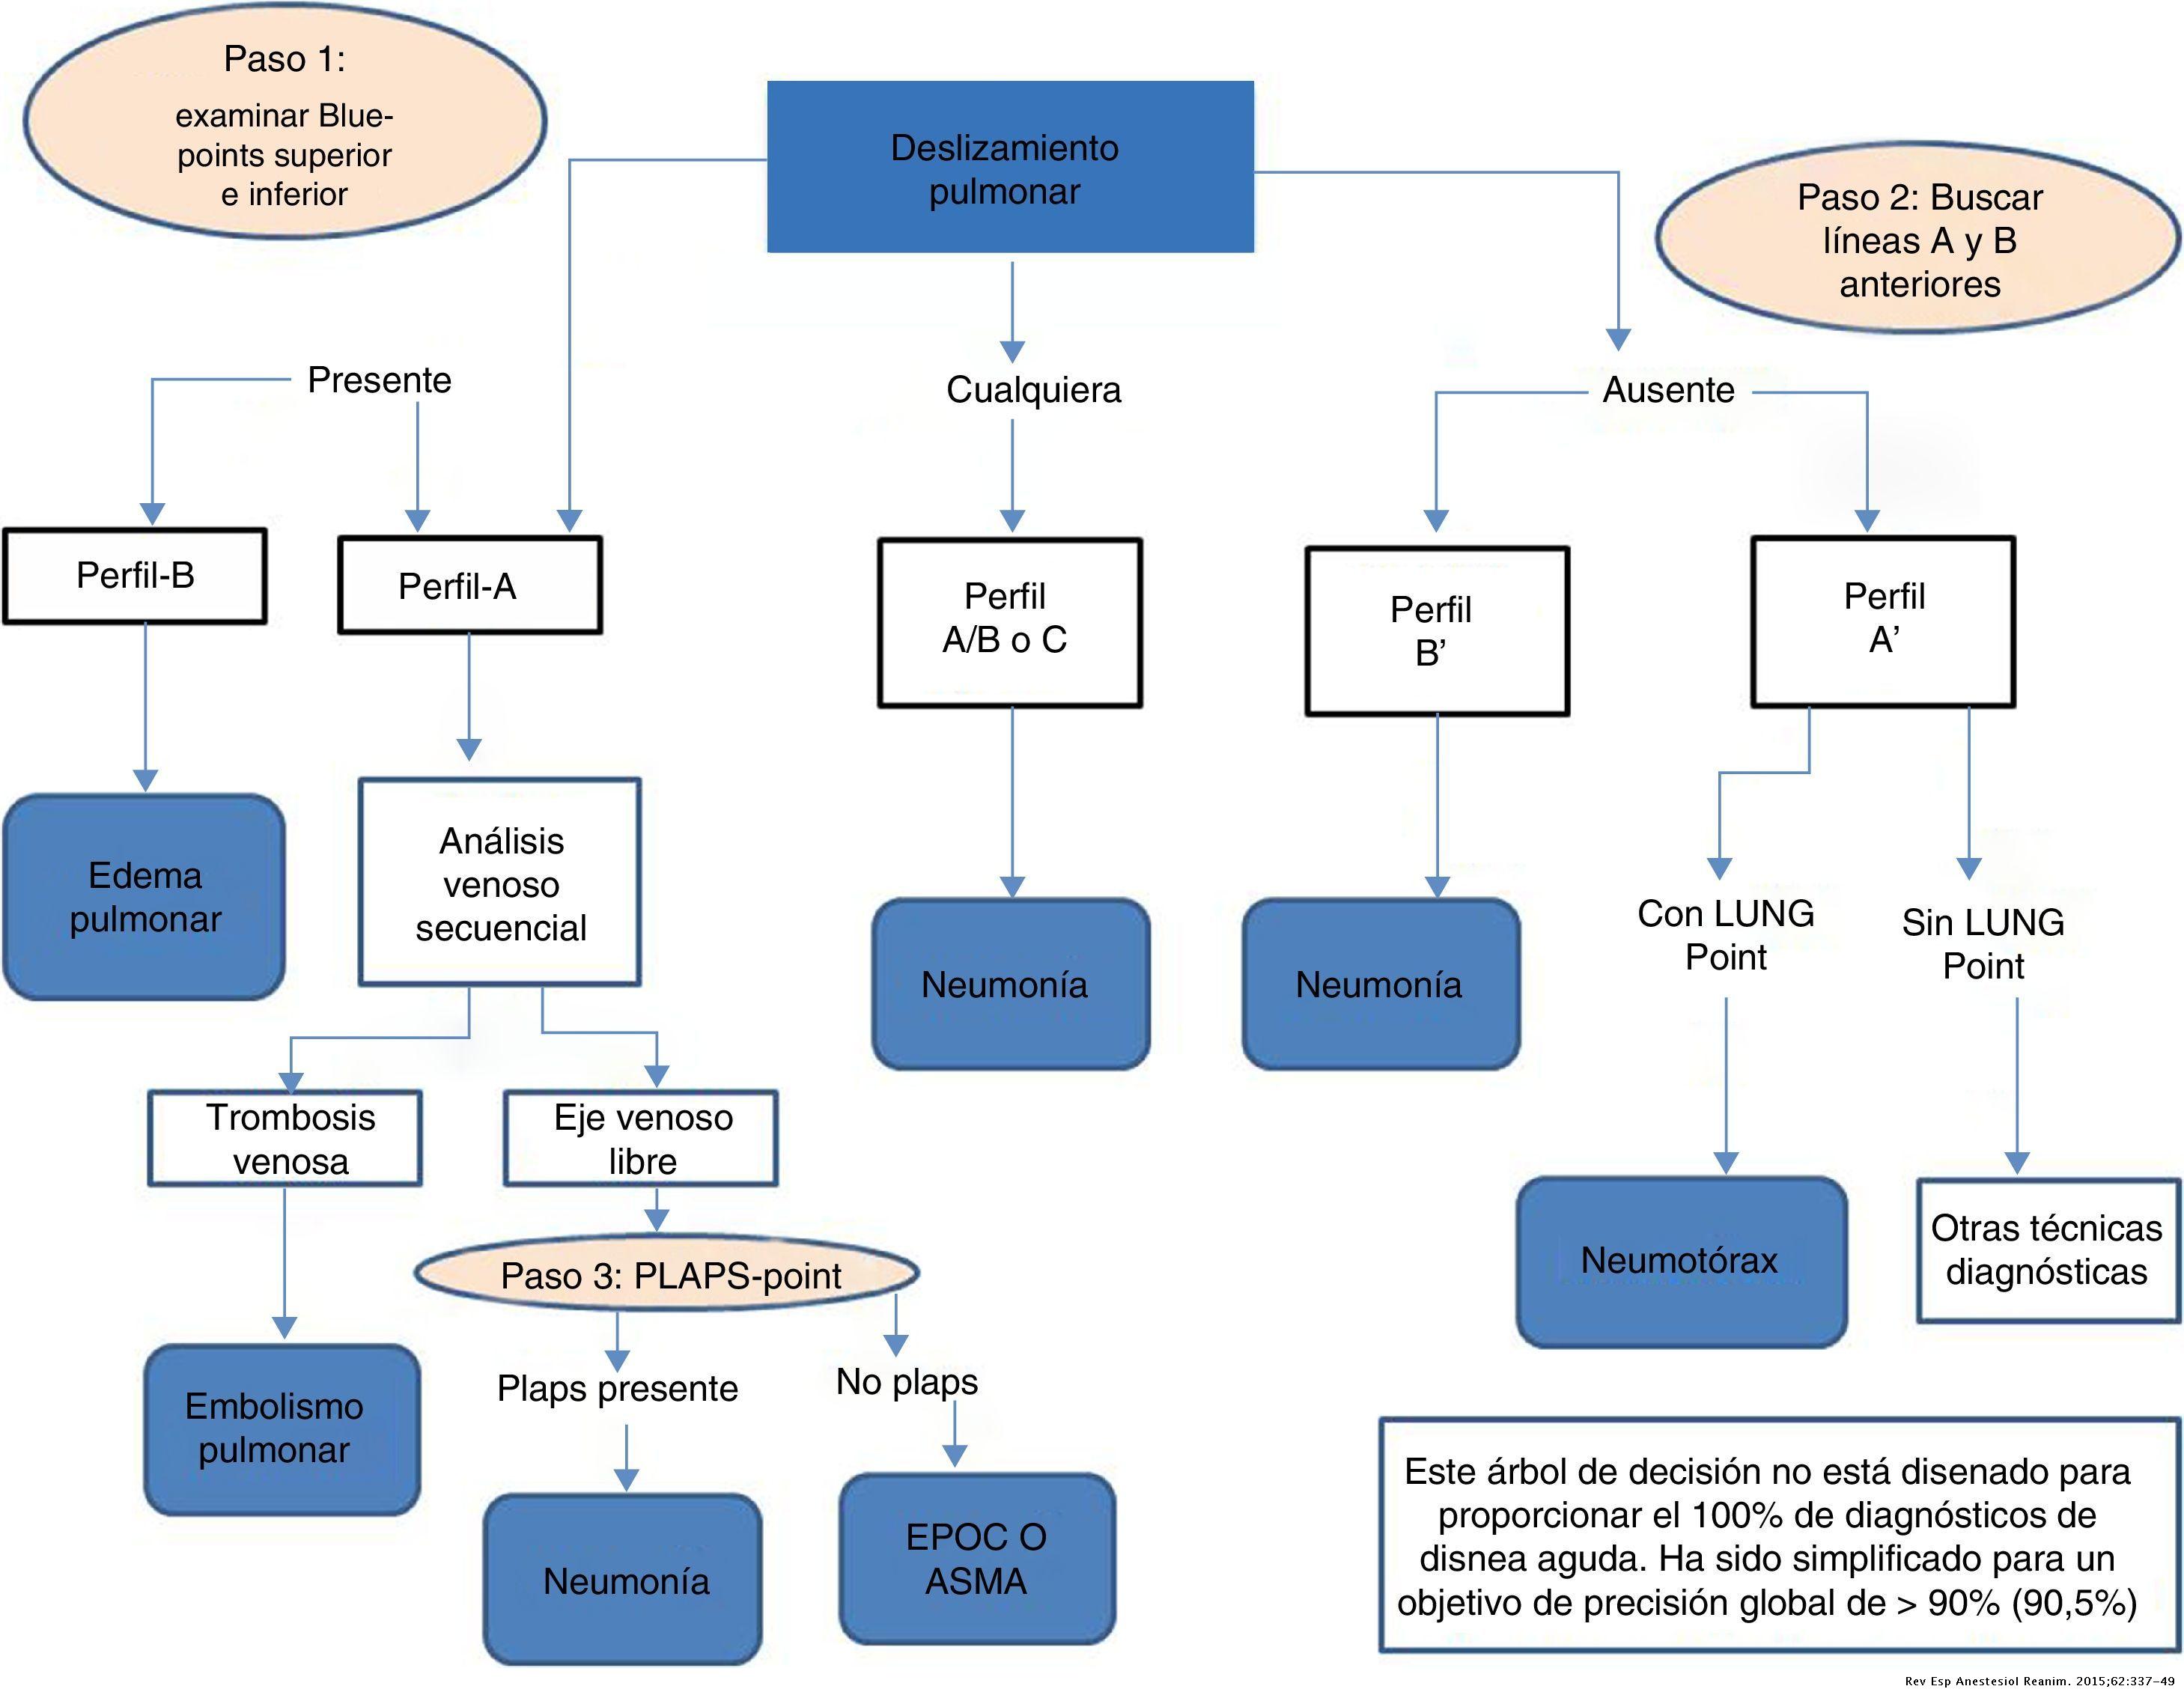

La disnea produce un cuadro de insuficiencia respiratoria normalmente causada por neumotórax, ASMA/EPOC, neumonía, insuficiencia cardíaca o embolismo pulmonar.

En la ecografía pulmonar observamos unos patrones ecográficos (normal, deslizamiento pleural, líneas A, líneas B, derrame pleural y consolidación pulmonar). Realizando una serie de preguntas dicotómicas sobre estos patrones ecográficos se establece un algoritmo (protocolo BLUE) que permite establecer con alta sensibilidad y especificidad la causa de la disnea mediante un árbol de decisión.

Aplicando dicho protocolo establecemos un diagnóstico ecográfico de presunción de Edema Agudo de Pulmón/Insuficiencia cardíaca.

El protocolo BLUE es utilizado normalmente en servicios de urgencias para valorar al paciente con disnea aguda, estableciendo el diagnóstico con una precisión superior al 90%.